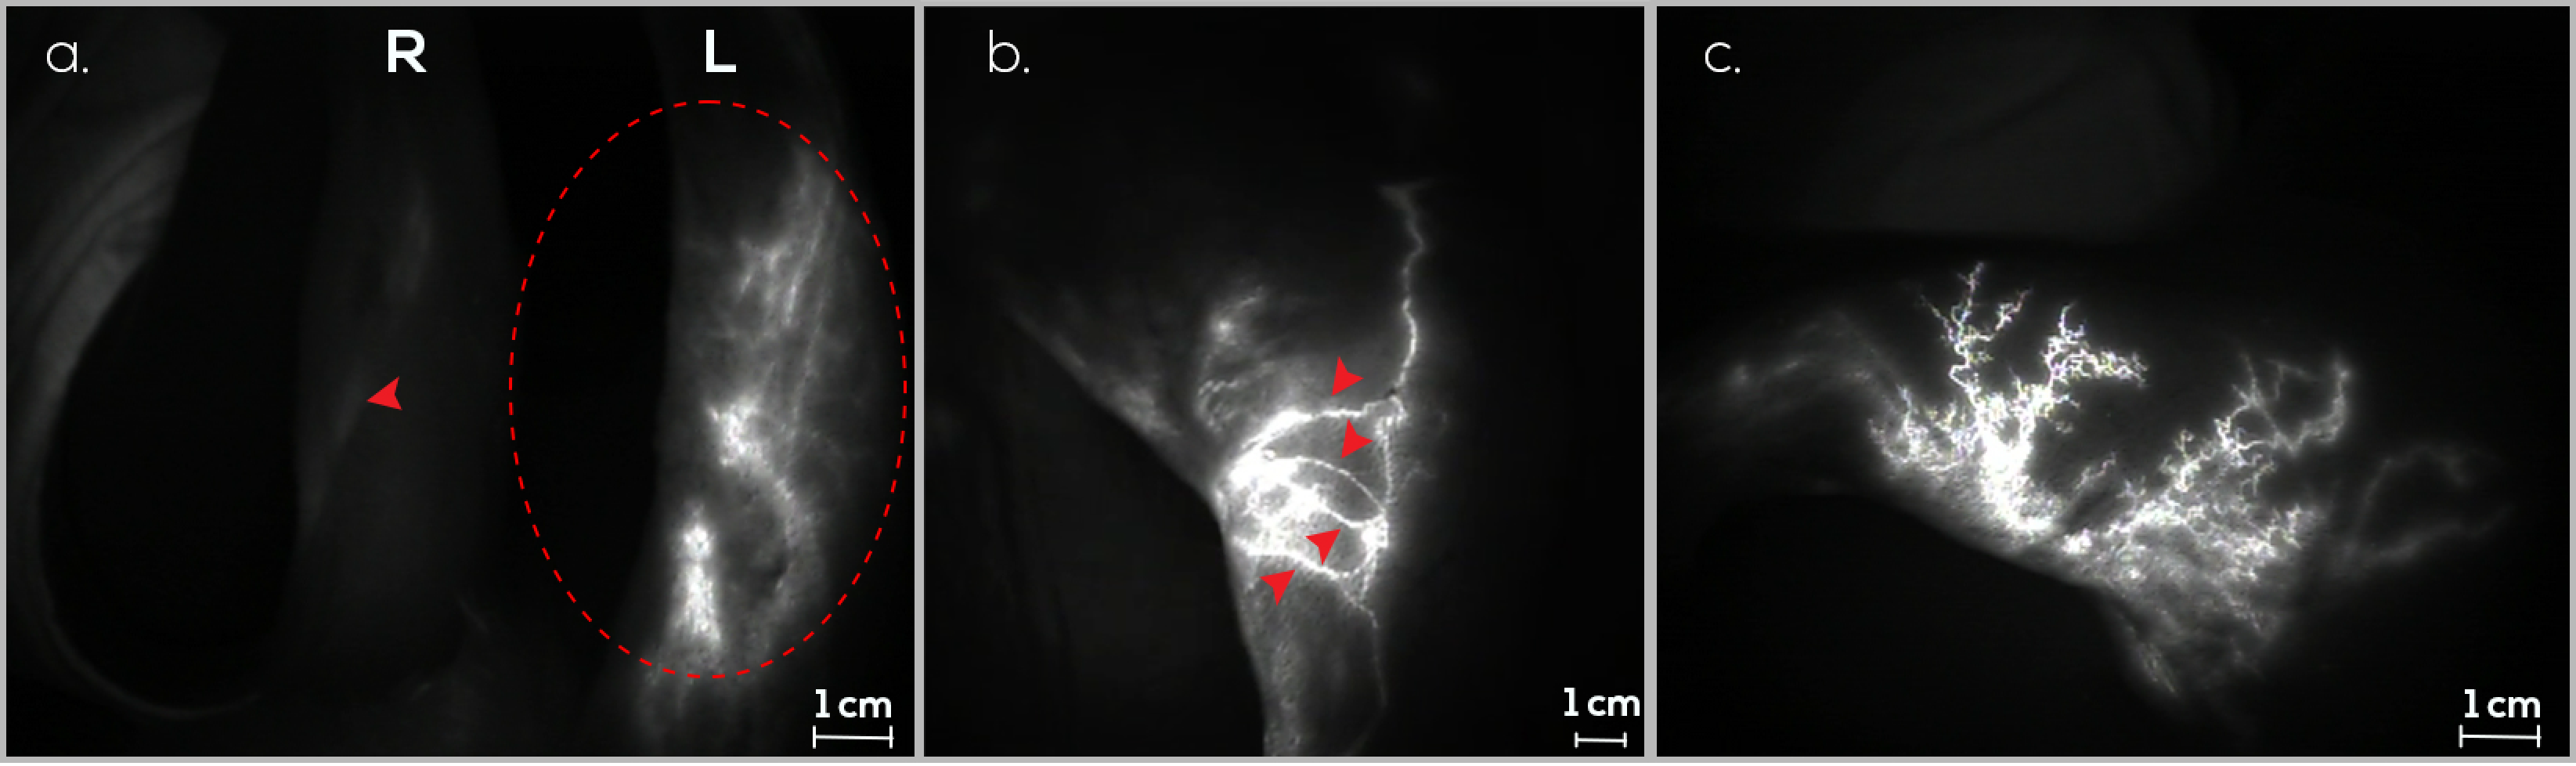

3.1. Treatment Group (G1)

3.2. Preventive Group (G2)

3.3. Control Group (G3)

3.4. Follow-Up Assessments